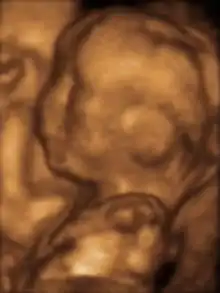

3D ultrasound

Modern 3D ultrasound images provide greater detail for prenatal diagnosis than the older 2D ultrasound technology.[6] While 3D is popular with parents desiring a prenatal photograph as a keepsake,[7] both 2D and 3D are discouraged by the FDA for non-medical use,[8] but there are no definitive studies linking ultrasound to any adverse medical effects.[9] The following 3D ultrasound images were taken at different stages of pregnancy:

- 3D Ultrasound of fetal movements at 12 weeks

75-mm fetus (about 14 weeks' gestational age)

Fetus at 17 weeks

Fetus at 20 weeks